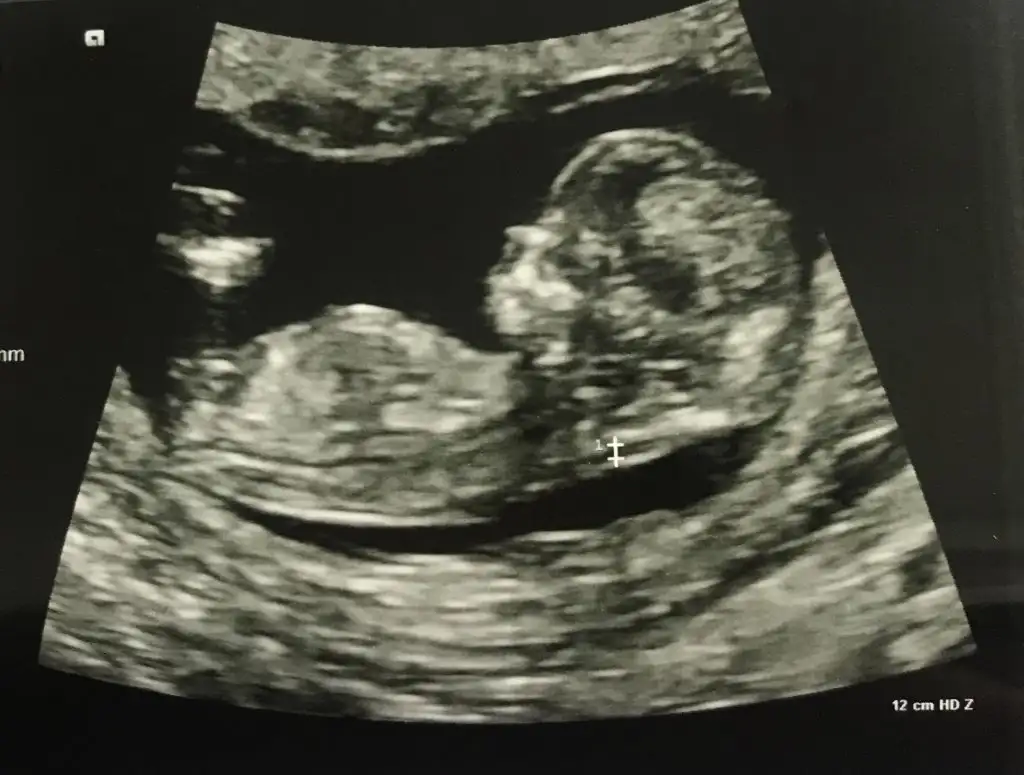

Kıza benzettimEki Görüntüle 2710264 banada tahmin yaparmisiniz lütfen![]()

Eki Görüntüle 2710264 banada tahmin yaparmisiniz lütfen![]()

Canım senin bebiş erkeğe benziyorEki Görüntüle 2710264 banada tahmin yaparmisiniz lütfen![]()

TeşekkürlerBence kız gibi![]()

Erkek gibi sanki